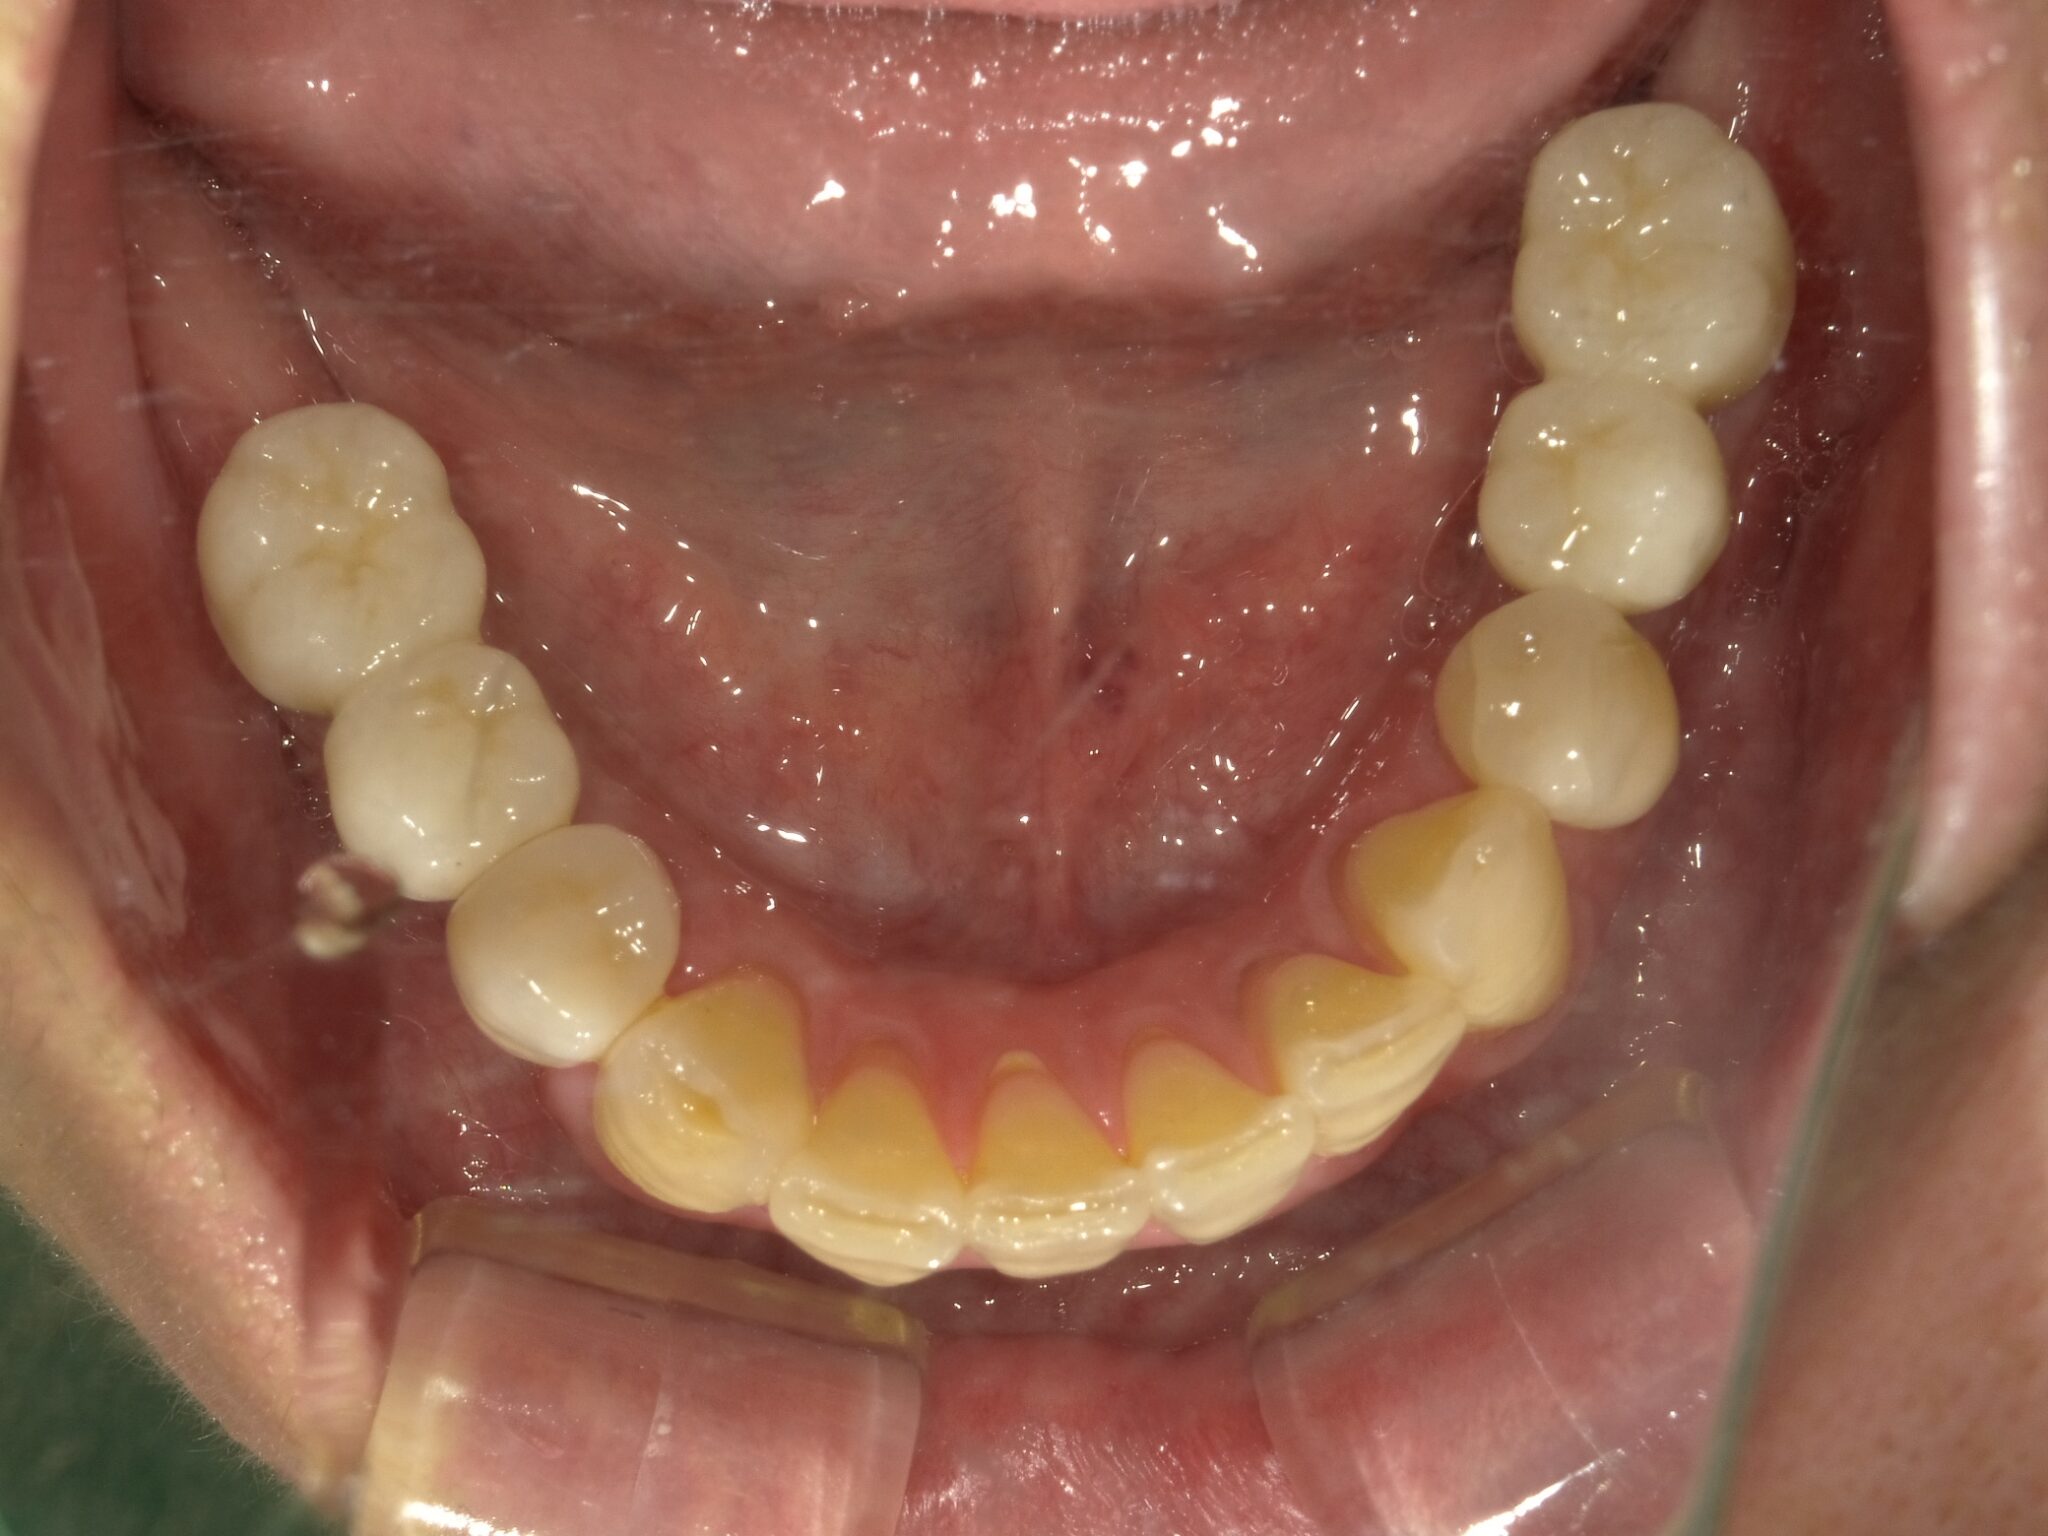

| 主訴 | 全体的に見た目を綺麗にしたい。奥歯でしっかり噛みたい。 |

| 治療内容 | インプラント埋入(左下5・6,右下5・6,左上4・6) サイナスリフト(左上4・6) ジルコニアBr(右上6−左上3) E –MAX CAD(右下4) セラミックインレー(左下4) |